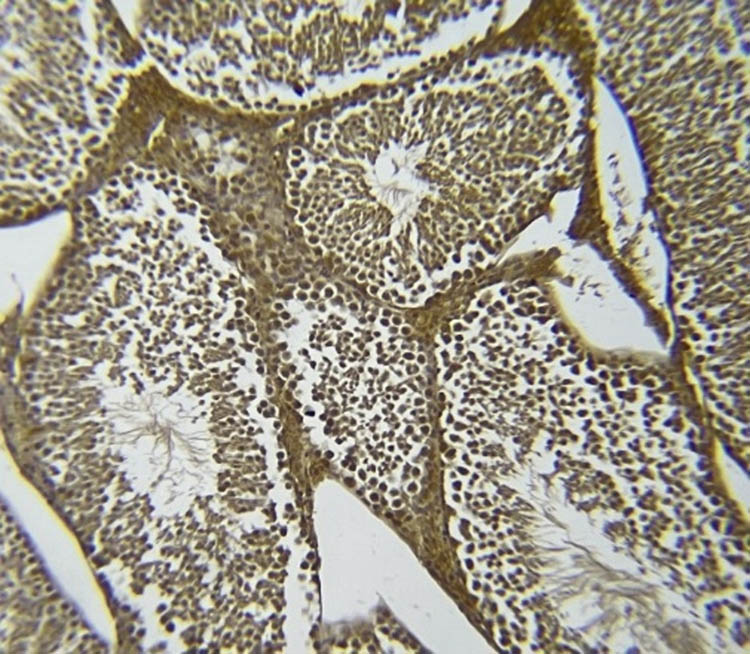

3.8 NOS immunohistochemistry in testicular tissue

Figures 7–11 represent the immunoreactivity of NOS in all groups. The immunoreactivity of NOS was significantly greater in mice treated with CGS (Figure 8), CGM (Figure 9), and CGA extracts (Figure 10) than in the control (Figure 7) and untreated diabetic (Figure 11) groups. In the untreated diabetic group, normal testicular architecture (seminiferous tubules) was destroyed and replaced by adipose tissue. Furthermore, the immunoreactivity of the enzyme in the untreated diabetic group was the lowest (Figure 11). Treatment with different C. gileadensis extracts restored the normal architecture of testicular tissue in diabetic mice.

NOS immunoreactivity in the diabetic C. gileadensis sap-treated group.

NOS immunoreactivity in the diabetic C. gileadensis methanol-treated group.

NOS immunoreactivity in the diabetic C. gileadensis acetone-treated group.

NOS immunoreactivity in the untreated diabetic group.